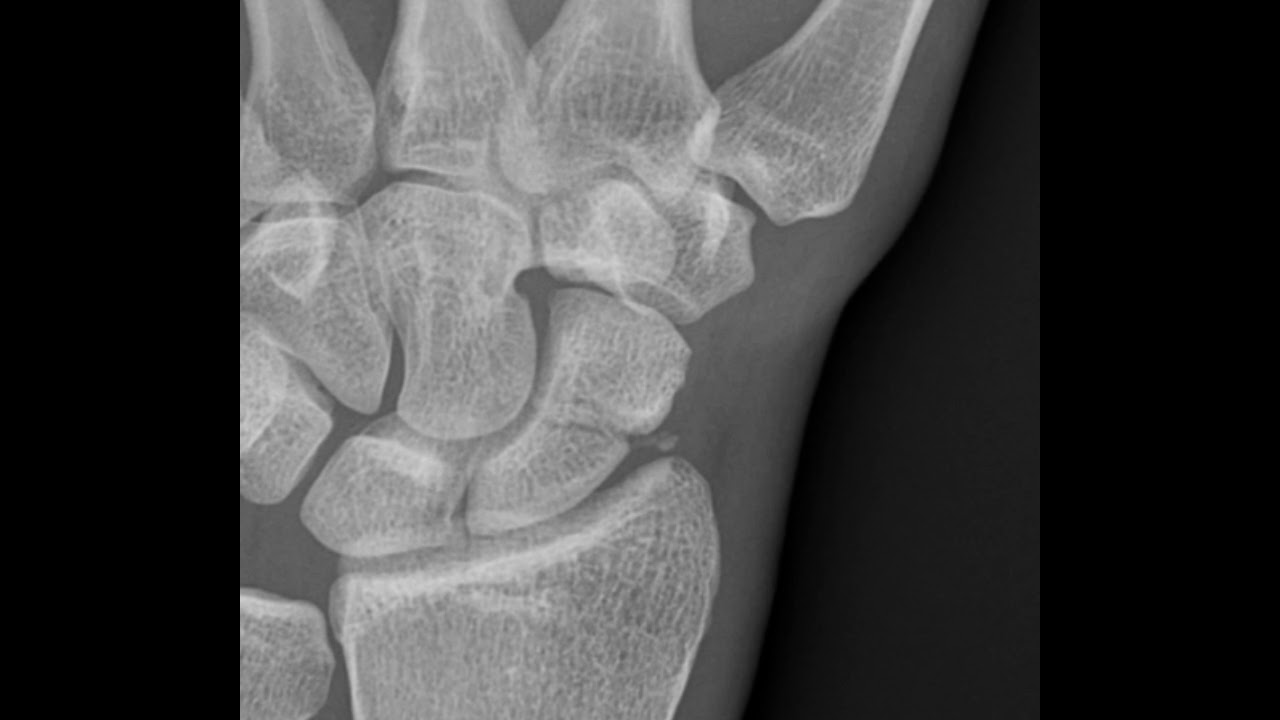

Scaphoid Fracture (Xray 2) YouTube

Scaphoid Fracture (Xray 2) YouTube Scaphoid Fracture Cast Youtube An animated description of scaphoid fractures (broken wrist bone) and treatment options.visit. A person may need a cast for a scaphoid fracture, with or without surgery. Identify the common mechanisms of injury that lead to scaphoid fractures. Summarize appropriate evaluation and examination procedures, including diagnostic imaging,. Does a scaphoid fracture require a cast? Symptoms of a scaphoid fracture typically include. Scaphoid Fracture Cast Youtube.

[Figure, Wrist Radiograph, Scaphoid Fracture] StatPearls NCBI Bookshelf Scaphoid Fracture Cast Youtube Ebraheim’s educational animated video describes fractures of the scaphoid carpal bone. See what a scaphoid fracture looks like and hear dr. A person may need a cast for a scaphoid fracture, with or without surgery. An animated description of scaphoid fractures (broken wrist bone) and treatment options.visit. Identify the common mechanisms of injury that lead to scaphoid fractures. Warhold describe. Scaphoid Fracture Cast Youtube.